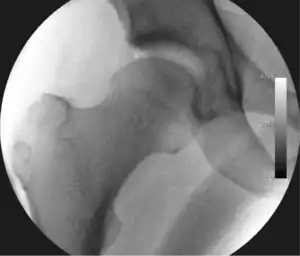

Figure 3. Fluoroscopic picture showing a mild amount of distraction of the hip before insertion of any instruments

The procedure is performed with the patient asleep (general anaesthetic) or under spinal anaesthesia. There are two widely used methods, one with the patient on their back (supine) and the other on their side (lateral decubitus). Which is used is down to the surgeon's preference. To gain access to the central compartment of the hip joint (between the ball and socket), traction is applied to the affected leg after placing the foot into a special boot. (See fig. 2) There is specifically designed equipment for this, although some surgeons use a 'traction table', initially designed to help in the operative fixation of broken thigh and lower leg bones. The amount of traction (or pull) needed is assessed with the help of fluoroscopy (low-dose portable x-ray). (See fig. 3) It is usually not possible to distract the ball from the socket with traction alone by more than a few millimetres. Once the surgeon is happy that they will be able to gain access to the hip joint (i.e. the ball will distract from the socket by a small amount), the patient is then painted with antiseptic and the surgical drapes applied.

The next step is to insert a fine needle under x-ray guidance into the hip joint. This breaks the 'suction seal' of the joint and allows further distraction if necessary (see fig 4). The surgeon wishes to see the ball move out the socket by approximately 1 cm, so that access to the hip joint can be achieved with minimal risk of damage to the joint surfaces. Most surgeons will inject fluid into the joint at this stage, again to ensure that there is enough space between the ball and socket for safe instrument access. This needle is then removed. The next step is placement of the 'portals', or the small holes made to pass instruments into the joint. This is achieved by again passing a fresh hollow needle into the joint under x-ray control, usually in a slightly different position. The reason for this is so the surgeon can ensure that the needle, and subsequent cannulae do not penetrate and damage the acetabular labrum or cartilage joint surfaces (see fig. 5). Again, surgeons will have their own preferences as to their preferred placement. Through this hollow needle, a long thin flexible guide wire is passed into the joint, and the needle is removed over it, leaving the guide wire in situ. A small cut in the skin is made around the wire, to allow for larger cannulae to be placed over the wire through the portal. The wire therefore guides the larger cannulae into the joint. The most common external diameters of cannulae used are between 4.5 and 5.5 mm. Once the surgeon is satisfied that the cannula is in the correct position, by a combination of feel and x-ray guidance, the guide wire can be withdrawn. Once the first portal is correctly placed, any further portals may be created once the camera is in position, to ensure that they are placed with minimal risk to the joint surfaces. This process can be repeated to gain as many points of entry to the hip joint as the surgeon requires, normally between two and four. Certain of these entry points will be used for the viewing arthroscope and others for operating instruments.